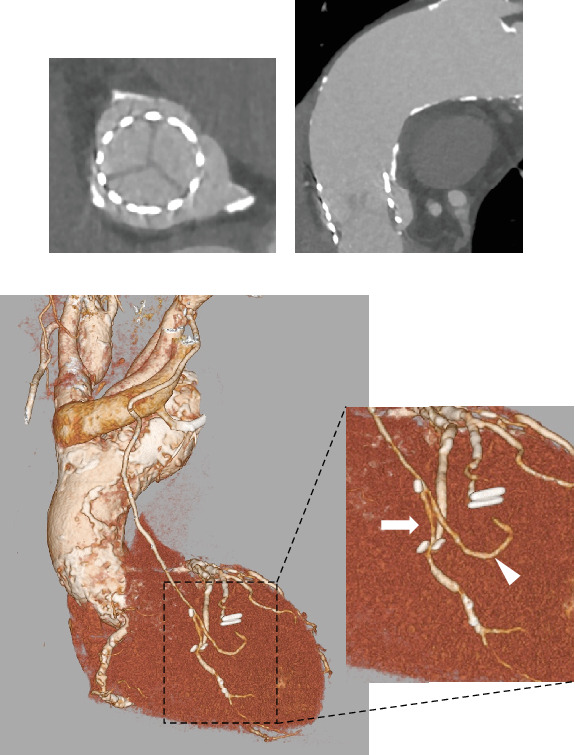

Patients on hemodialysis with concomitant severe aortic stenosis (AS) and multivessel coronary artery disease (CAD) are at high risk for surgical aortic valve replacement (SAVR) and coronary artery bypass grafting (CABG). Transsubclavian-transcatheter aortic valve implantation (TSc-TAVI) is a well-established alternative approach to transfemoral TAVI for patients with unfavorable femoral access. Herein, we report a case in which minimally invasive surgical treatment and TSc-TAVI were performed simultaneously in a patient with severe AS and multivessel CAD undergoing hemodialysis. An 85-year-old man undergoing hemodialysis for end-stage renal disease owing to severe AS (mean pressure gradient, 46 mmHg; aortic valve area, 0.75 cm2; and left ventricular ejection fraction, 59%) presented to our hospital with chest pain on exertion. Preoperative coronary angiography revealed significant stenosis of the left anterior descending (LAD) coronary artery and right coronary artery (RCA), requiring revascularization. However, the patient was not a good candidate for transfemoral TAVI because of a porcelain ascending aorta and a shaggy descending aorta observed on computed tomography. He was scheduled for concomitant right TSc-TAVI and minimally invasive cardiac surgery (MICS)-CABG after percutaneous coronary intervention (PCI) for the RCA. The treatment was successful. Simultaneous TSc-TAVI and MICS-CABG with PCI may be applied as a minimally invasive surgical treatment modality for patients with AS and CAD undergoing hemodialysis.